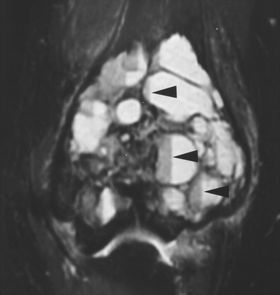

动脉瘤样骨囊肿是溶骨性的,通常是扩张的病变,最常见于长骨的干骺端。它们出现在较年轻的一组(通常在5至20岁之间),在年龄上与巨细胞瘤重叠较小。如果囊肿在骨膜闭合后发生或持续存在,那么它可能延伸到骨骺并且与巨细胞瘤无法区分(图9A)。CT或MRI可显示液体水平,代表血液分层(图9B)。缺乏增强固体成分也将支持巨细胞瘤与动脉瘤样骨囊肿的鉴别。

图9B。-13岁女孩,动脉瘤样骨囊肿。T2加权冠状STIR图像显示具有多种液体水平(箭头)的多囊性病变,典型的动脉瘤样骨囊肿。